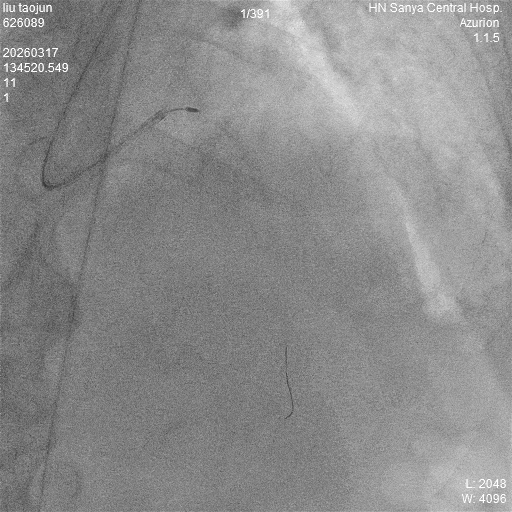

手术中,医生使用一枚高速旋转的、带有钻石颗粒的旋磨头,以每分钟十几万转的速度,像“金刚钻”一样将血管内的钙化斑块磨碎,为支架植入打开了一条畅通的“绿色通道”。在成功“旋磨”打通血管后,团队精准定位,成功植入了3枚支架。

▲旋磨过程